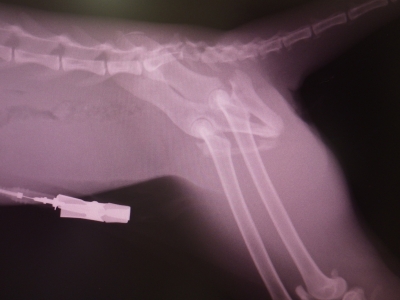

犬と猫の大腿骨の骨折例 - 動物病院 東浦町・大府市・刈谷市|獣医